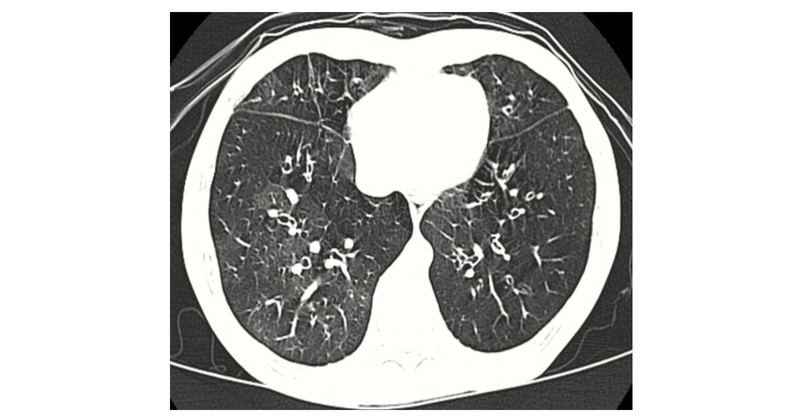

HRCT showing mosaic perfusion clinches the diagnosis.

Figure showing tile like “mosaic” pattern